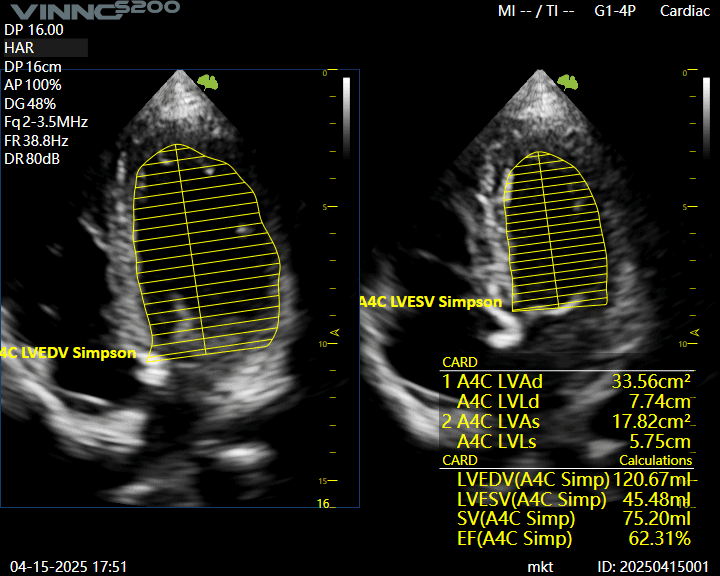

Auto EF – fractia de ejectie, cu un singur click.

Ecograf VINNO S200 – solutie moderna pentru evaluari zilnice

Ecograf VINNO S200 – solutie moderna pentru evaluari zilnice Echipa Numeris Medical a finalizat cu succes instalarea ecografului VINNO S200 in cabinetul domnului dr. Ipate Florin, medic specialist cardiologie din Calarasi.In cardiologie, claritatea imaginii, stabilitatea semnalului si sensibilitatea Doppler sunt…